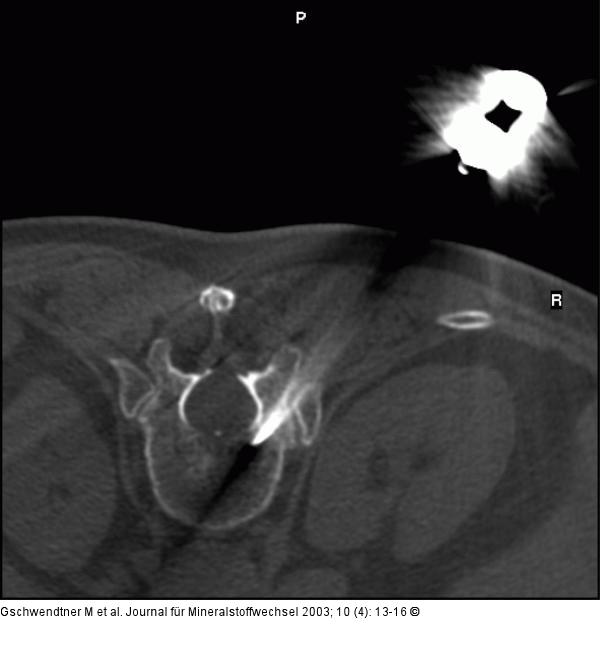

Abbildung 2: Vertebroplastie - Wirbelkörperpunktion Interkostovertebraler Zugangsweg. |

Abbildung 2: Vertebroplastie - Wirbelkörperpunktion

Interkostovertebraler Zugangsweg. |